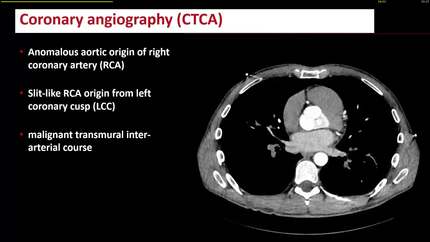

Isolated ventricular arrhythmia in a 43-year-old athlete: managing sports and cardiac risk